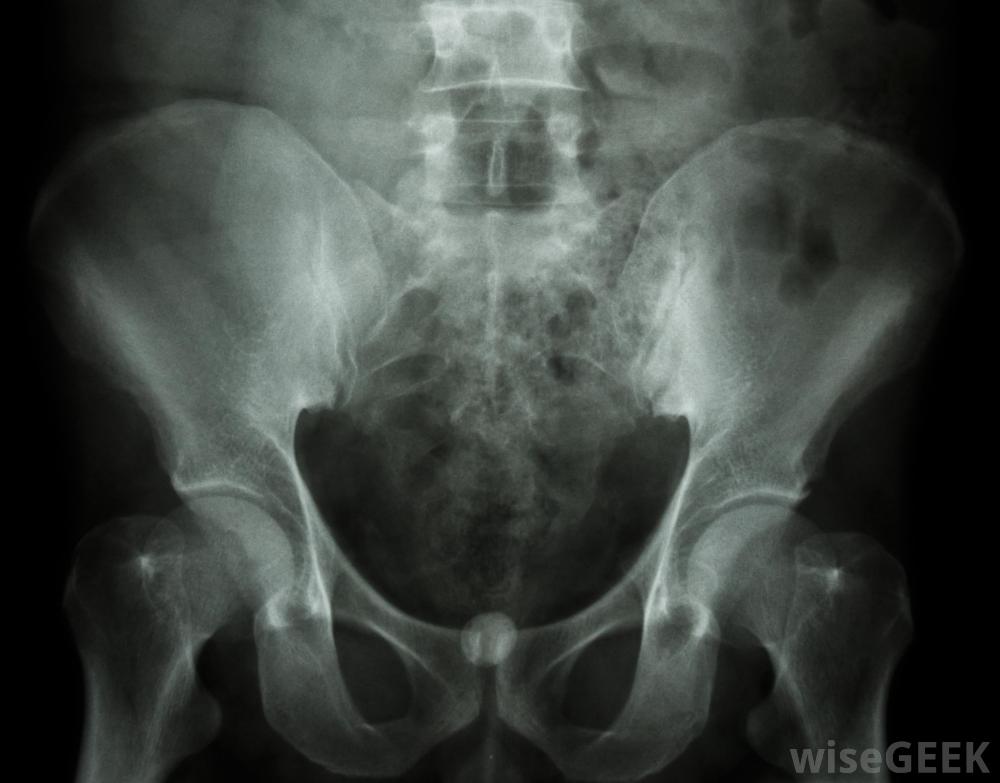

尿流計是一種診斷性試驗,用于檢查病人尿液的量或流速是否異常。該程序簡單明了,無痛,只需將尿液放入電子量表上的漏斗裝置中。醫生通常使用尿流率來檢查可能的膀胱阻塞,腎臟問題,前列腺肥大和尿路感染。不尋常的檢查結果表明需要額外的檢查程序,例如x光片和實驗室樣本分析。經常出現泌尿系統問題的人患膀胱癌的風險可能會增加在大多數情況下,泌尿科醫生或初級保健醫生會在進行體檢并詢問患者的身體癥狀后決定進行尿流量測定。由于需要采取某些措施進行準備,所以通常不在初次評估的同一天進行醫生可以在尿流率測定前解釋程序并告知病人他或她需要做什么。確切的說明可能會有所不同,但大多數醫生建議人們在檢查前48小時避免服用非必需藥物,以確保準確的結果。此外,在檢查的早晨,人們需要喝幾杯水,這樣他們的膀胱就會滿了。當尿流量測量讀數異常時,可能會進行血液檢測在進行尿流量測定的那天,醫生可以向病人解釋程序,并告訴病人如何使用儀器。量表和漏斗連接在私人浴室的馬桶上。在小便前大約5秒鐘,病人按一下按鈕打開量表。然后他或她便往漏斗里小便,試著在不用力或停止的情況下正常操作。小便后,再次按下按鈕關閉計量器。然后護士或醫生取出設備并讀取結果。大多數醫生都會告訴患者在尿流率測定前48小時內避免任何非必要的藥物治療。檢測結果顯示尿量,排出率,以及膀胱完全排空所需的時間。量表通常以毫升每秒(毫升/秒)為單位進行報告。結果可以與某些年齡段的男性和女性的既定平均值進行比較,以確定其是否正常。例如,65歲以上男性的平均流速約為9毫升/秒。如果患者的尿流量測定結果在5毫升/秒左右,醫生可以自信地懷疑前列腺肥大或其他常見疾病阻礙了正常的尿流異常發現可能表明需要進行實驗室分析當尿流量測定讀數異常時,會進行診斷性影像檢查、額外的身體檢查以及血液和尿液檢查。根據個人的具體問題,可能需要藥物治療、物理治療或手術治療。通常,在整個治療過程中,尿流量測定會定期重復進行為了確定癥狀是否正在改善。如果患者的尿流量測定結果在5毫升/秒左右,醫生可能會懷疑前列腺肥大醫生通常使用尿流量測定法檢查尿路感染。尿流量測定的異常結果可能會導致額外的檢查,比如X光。